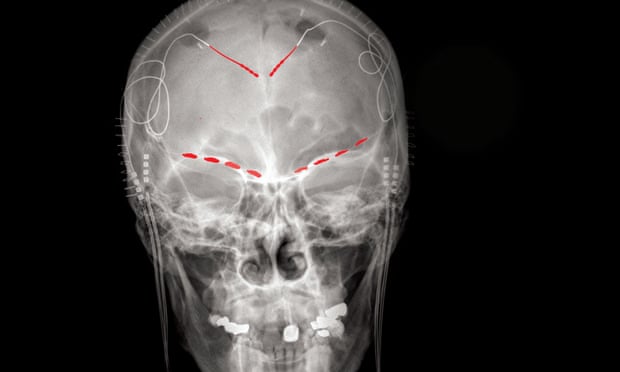

Nature Neuroscience, Shirvalkar and colleagues surgically implanted electrodes in four patients with excruciating pain after stroke or loss of limb. The device allows patients to record activity in two brain regions (anterior cingulate cortex (ACC) and orbitofrontal cortex (OFC)) by pressing buttons on the remote control.

Volunteers were asked to complete short questionnaires about the severity and type of pain they experienced several times a day, and photographs of their brains were recorded. Armed with feedback and brain recordings, the researchers discovered that they could develop an algorithm to predict the patient based on the electrical signals in the OFC. "We developed a biomarker target for this disease," said Shirvalkar. Independent study by the

These findings could have immediate implications for clinical trials that are also working on a technique called deep brain stimulation to manage chronic pain. The deep brain sends electrical impulses to the brain to stop the problem. DBS is a treatment of last resort as it includes neurosurgery, but is already used to treat Parkinson's disease and major depression. To be effective, doctors need to know exactly what the signs are for purpose.